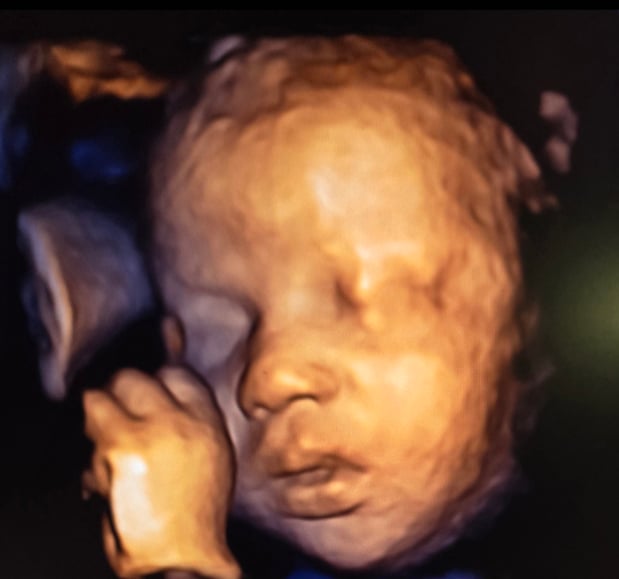

Tasha Crump, is registered by the American Registry of Diagnostic Medical Sonographers (ARDMS) and have over 18 years experience in medical diagnostic sonography specializing in Maternal Fetal Medicine. She is a highly proficient in the art of 3D 4D ultrasound. Tasha has practiced and trained in NYC's top ranked hospitals including Columbia Presbyterian. At Love at First Sight Imaging Studio you'll be in a very comfortable and calming atmosphere for you and your family to bond with your baby. We have state of the art equipment with HD Live to image unbelievably realistic views of your baby. You will fall in Love at First Sight.